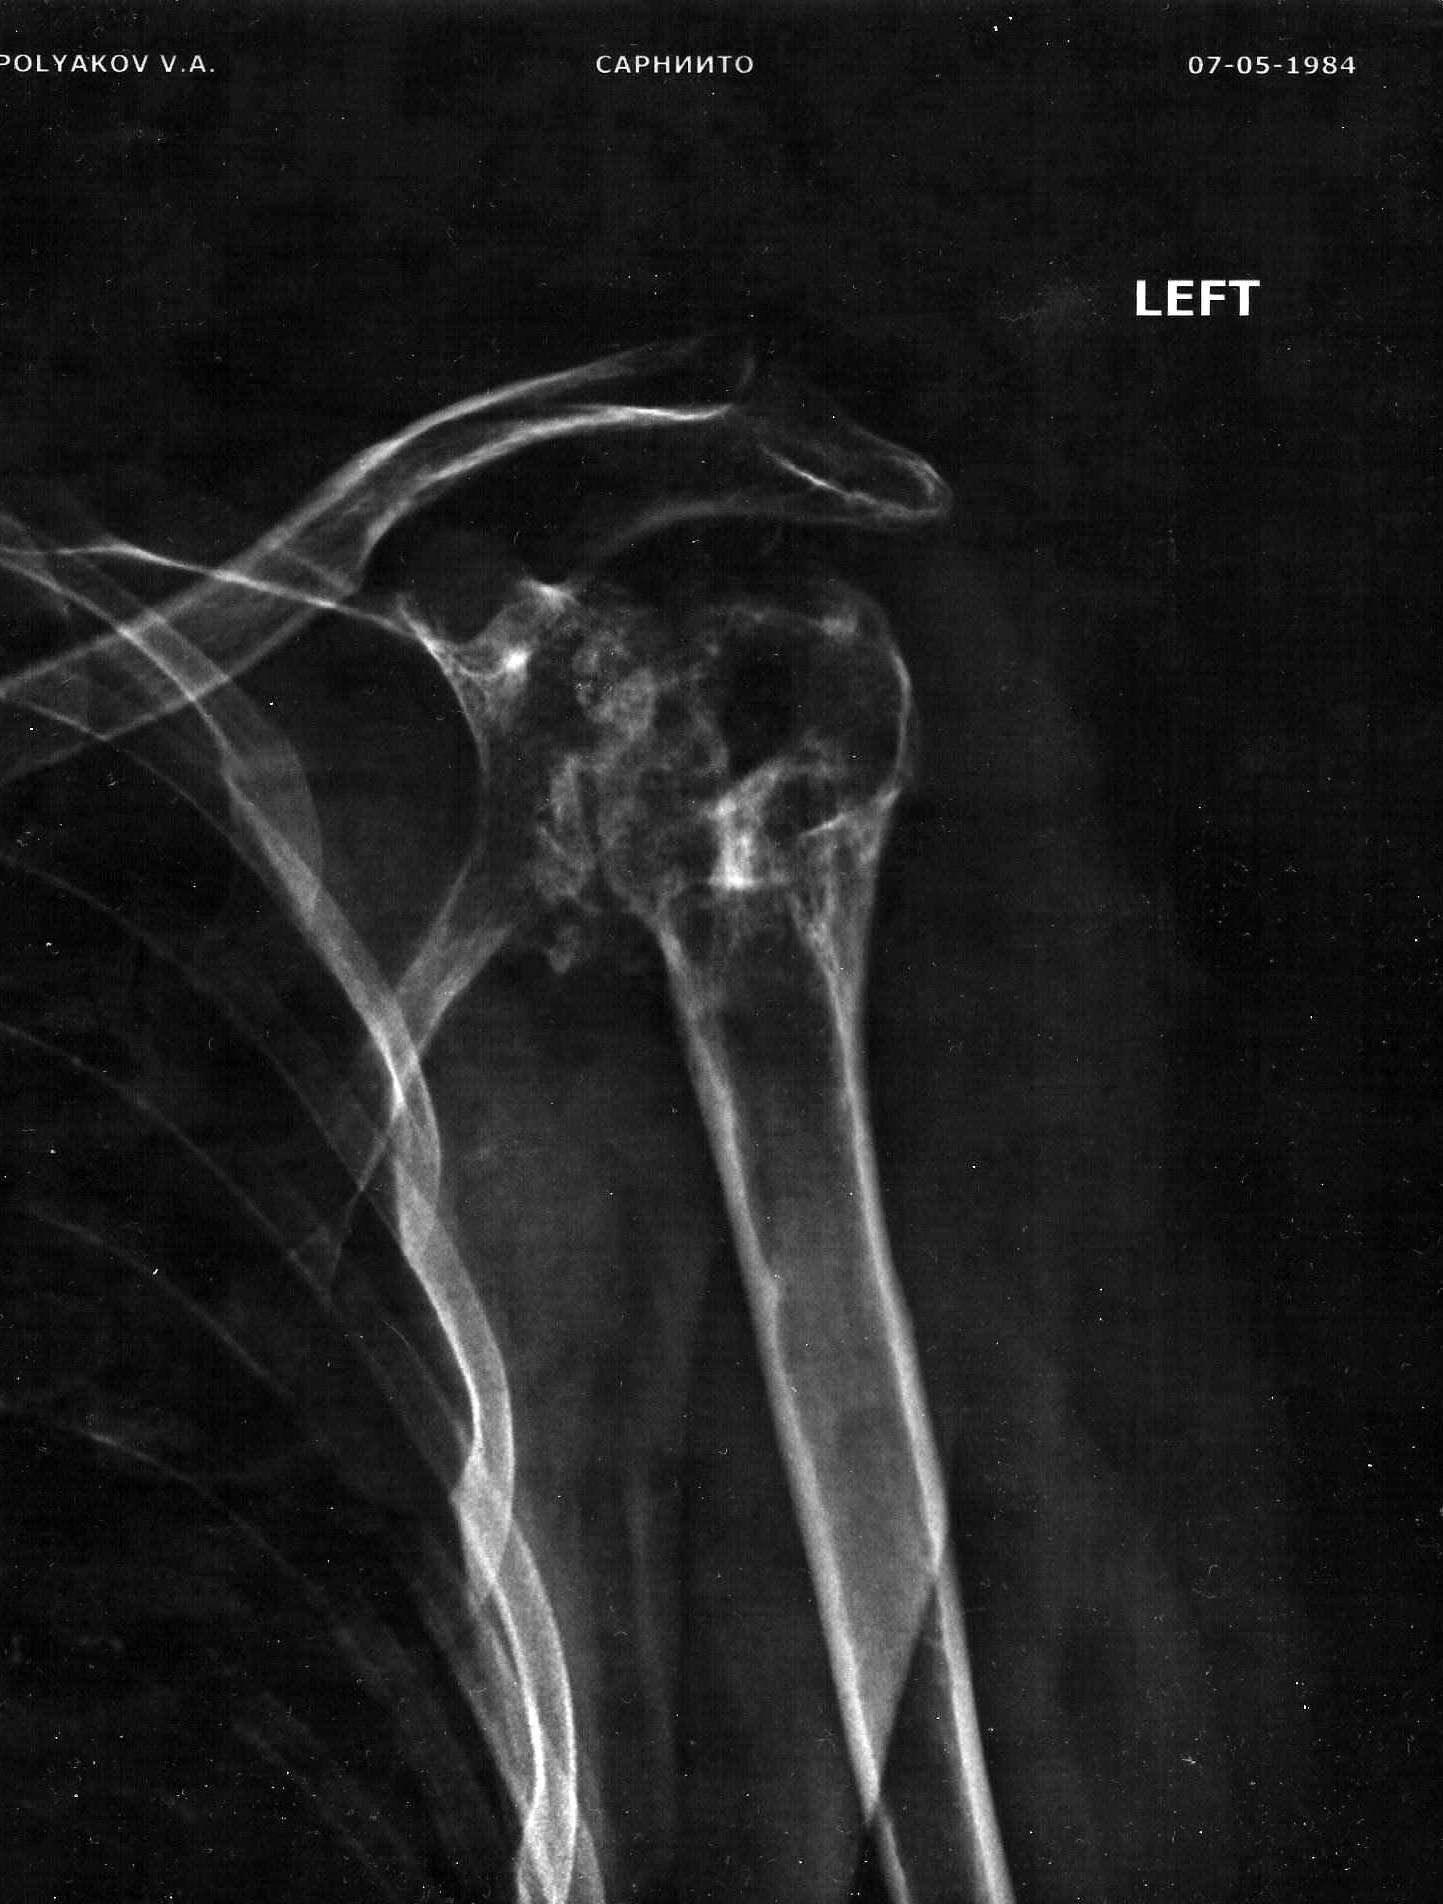

Уважаемые коллеги, добрый день. Подскажите, где возможно произвести протезирование плечевого сустава с наилучшим результатом? Мужчина 33 года. Травма от 2009 года - размозжение верхней трети плеча. Заживление вторичное. на протяжении 4 лет проводилось лечение остеомиелита головки левой плечевой кости с относительно удовлетворительным эффектом. Однако функция не восстановилась. в настоящий момент имеется ограничение функции на 50 %, выраженный болевой синдром без общей островоспалительной реакции. Рентгенография приложена. По данным КТ имеется: хронический остеомиелит, дегенеративно-дистрофичекие изменения левого плечевого сустава.